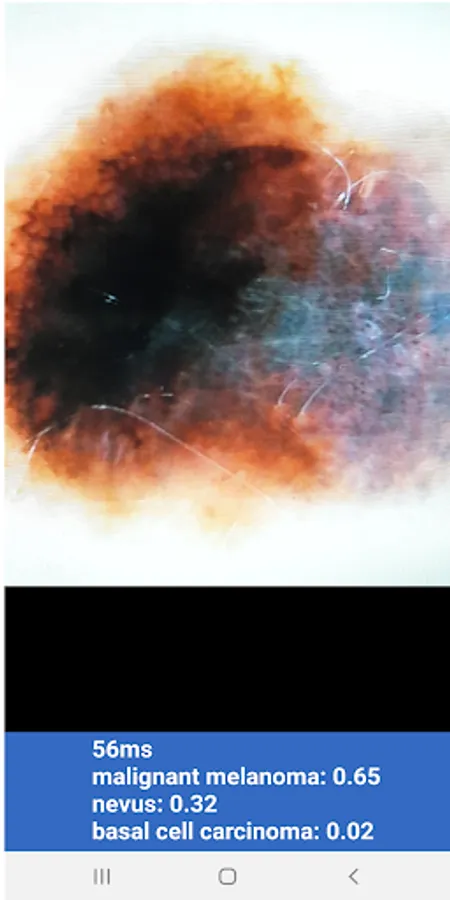

Artificial Intelligence diagnostics of dermatoscopic images using Google's open-source TensorFlow and its Android app TFLite. Based on the pre-trained neural network MobileNet trained on over 10.000 dermatoscopic images from isic-archive.com that are verified by Specialists in Dermatology.

It's simple to use and free, download the app and point it to a dermatoscopic image to get a probability for Malignant Melanoma, Basal cell carcinoma, Actinic keratosis, Seborrheic keratosis or Nevus.

DISCLAIMER: This app is intended for educational purposes only and it does not qualify nor is it intended as medical advice. You should seek the advice of a physician if you are worried about a skin lesion. You need a dermatoscope or images derived from one to benefit from the neural network.